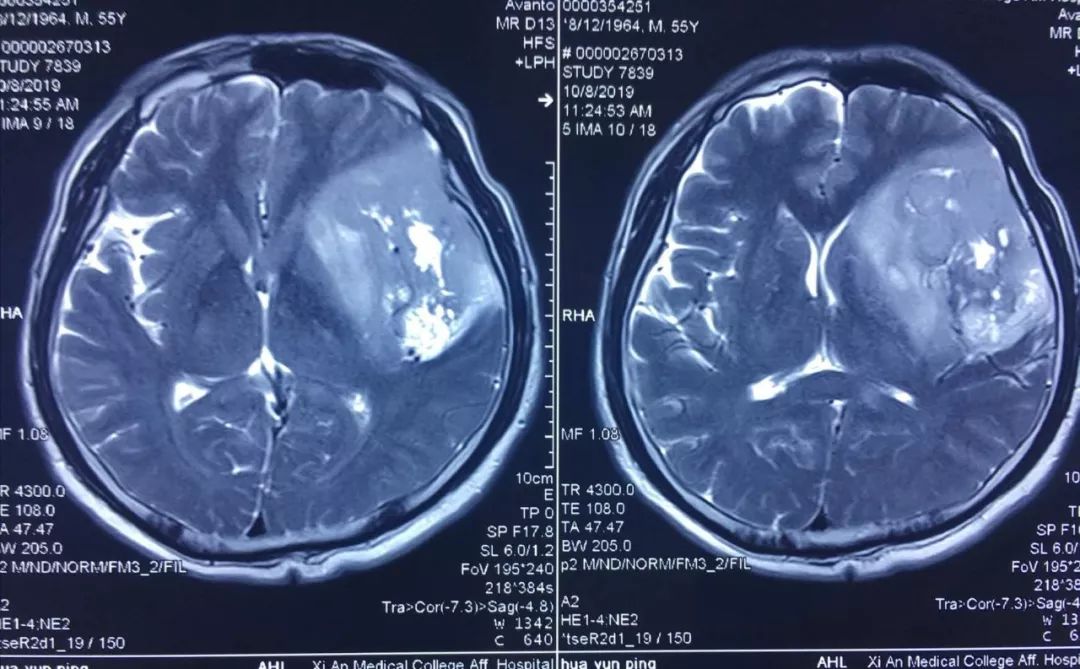

患者李某,今年55岁,因近年出现间歇性面部抽搐,一直未给予重视,近来发作频繁,经朋友建议在外院行头颅核磁检查,发现颅内巨大占位性病变,病变位于左侧额、颞和深部脑岛叶,达8.5×5.5×3cm,且侵犯语言功能区,颅内占位效应明显,中线偏移1cm,且肿瘤已经濒临脑疝边缘,如不及时进行手术干预,随时有脑疝可能,危及患者生命。

经多方了解后,在朋友的推荐下,患者慕名来到西安国际医学中心找到了脑科医院高国栋院长,高院长带领以贺世明主任为首的神经外科团队,对患者的病情及治疗方案等进行讨论,凭借多年的临床经验,结合患者影像结果判断为颅内胶质瘤,并建议尽快实施手术切除。